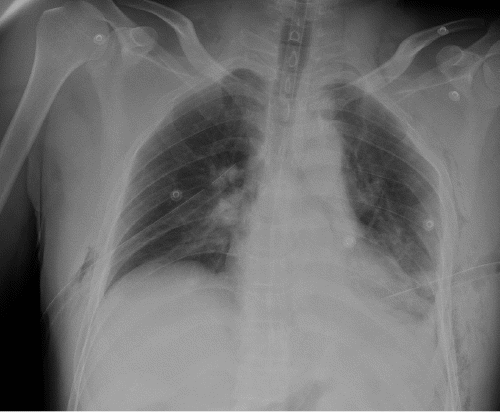

Figure 3. Portable Chest Radiography Showing Absence of Gastric Gas in Pericardium After Inserting Nasogastric Tube. Published with Permission